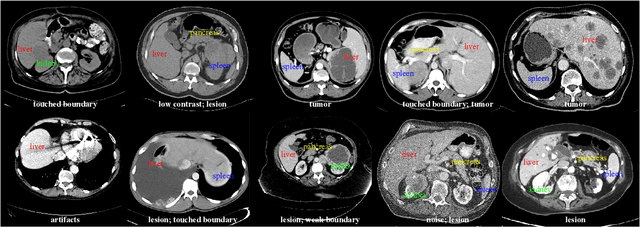

Abstract:Organ and cancer segmentation in abdomen Computed Tomography (CT) scans is the prerequisite for precise cancer diagnosis and treatment. Most existing benchmarks and algorithms are tailored to specific cancer types, limiting their ability to provide comprehensive cancer analysis. This work presents the first international competition on abdominal organ and pan-cancer segmentation by providing a large-scale and diverse dataset, including 4650 CT scans with various cancer types from over 40 medical centers. The winning team established a new state-of-the-art with a deep learning-based cascaded framework, achieving average Dice Similarity Coefficient scores of 92.3% for organs and 64.9% for lesions on the hidden multi-national testing set. The dataset and code of top teams are publicly available, offering a benchmark platform to drive further innovations https://codalab.lisn.upsaclay.fr/competitions/12239.

Abstract:Quantitative organ assessment is an essential step in automated abdominal disease diagnosis and treatment planning. Artificial intelligence (AI) has shown great potential to automatize this process. However, most existing AI algorithms rely on many expert annotations and lack a comprehensive evaluation of accuracy and efficiency in real-world multinational settings. To overcome these limitations, we organized the FLARE 2022 Challenge, the largest abdominal organ analysis challenge to date, to benchmark fast, low-resource, accurate, annotation-efficient, and generalized AI algorithms. We constructed an intercontinental and multinational dataset from more than 50 medical groups, including Computed Tomography (CT) scans with different races, diseases, phases, and manufacturers. We independently validated that a set of AI algorithms achieved a median Dice Similarity Coefficient (DSC) of 90.0\% by using 50 labeled scans and 2000 unlabeled scans, which can significantly reduce annotation requirements. The best-performing algorithms successfully generalized to holdout external validation sets, achieving a median DSC of 89.5\%, 90.9\%, and 88.3\% on North American, European, and Asian cohorts, respectively. They also enabled automatic extraction of key organ biology features, which was labor-intensive with traditional manual measurements. This opens the potential to use unlabeled data to boost performance and alleviate annotation shortages for modern AI models.

Abstract:With the unprecedented developments in deep learning, automatic segmentation of main abdominal organs (i.e., liver, kidney, and spleen) seems to be a solved problem as the state-of-the-art (SOTA) methods have achieved comparable results with inter-observer variability on existing benchmark datasets. However, most of the existing abdominal organ segmentation benchmark datasets only contain single-center, single-phase, single-vendor, or single-disease cases, thus, it is unclear whether the excellent performance can generalize on more diverse datasets. In this paper, we present a large and diverse abdominal CT organ segmentation dataset, termed as AbdomenCT-1K, with more than 1000 (1K) CT scans from 11 countries, including multi-center, multi-phase, multi-vendor, and multi-disease cases. Furthermore, we conduct a large-scale study for liver, kidney, spleen, and pancreas segmentation, as well as reveal the unsolved segmentation problems of the SOTA method, such as the limited generalization ability on distinct medical centers, phases, and unseen diseases. To advance the unsolved problems, we build four organ segmentation benchmarks for fully supervised, semi-supervised, weakly supervised, and continual learning, which are currently challenging and active research topics. Accordingly, we develop a simple and effective method for each benchmark, which can be used as out-of-the-box methods and strong baselines. We believe the introduction of the AbdomenCT-1K dataset will promote future in-depth research towards clinical applicable abdominal organ segmentation methods. Moreover, the datasets, codes, and trained models of baseline methods will be publicly available at https://github.com/JunMa11/AbdomenCT-1K.